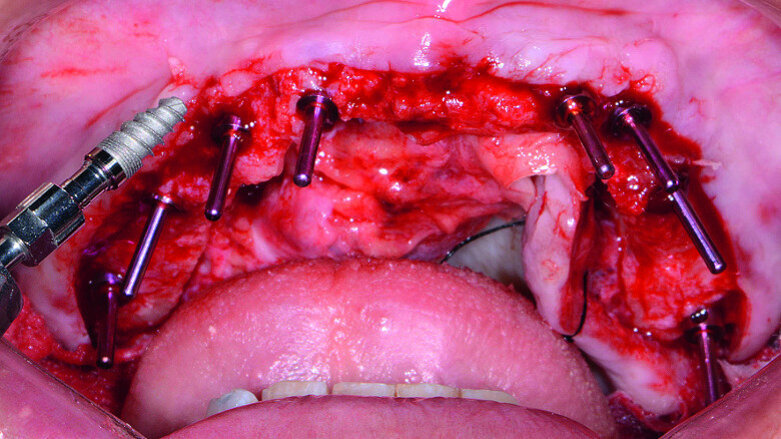

Fig. 13: Mandibular arch anaesthetised.

Fig. 14: Mandibular surgical guide stabilised.

Fig. 15: Implants and healing caps with surrounding grafting.

Next, the patient’s untreatable mandibular teeth (Fig. 13) were extracted using the Physics Forceps (GoldenDent), a flap was reflected, and an alveoloplasty was performed. A bone-supported guide was seated in order to control the location and angulation of the implant osteotomies (Fig. 14). As the Hahn Tapered Implants were threaded into place, their deep, sharp threads engaged the walls of the socket sites and helped maintain proper position toward the lingual aspect. Because of anticipated tissue swelling as a result of the bone levelling procedure, 5 mm high healing abutments were connected to the implants in the lower arch (Fig. 15). The immediate dentures were soft-relined with Mucopren (Kettenbach) to seat over the Hahn Tapered Implant Healing Abutments, the hourglass shape and undercuts of which provided a degree of retention that enhanced dental function for the patient during healing (Fig. 16).